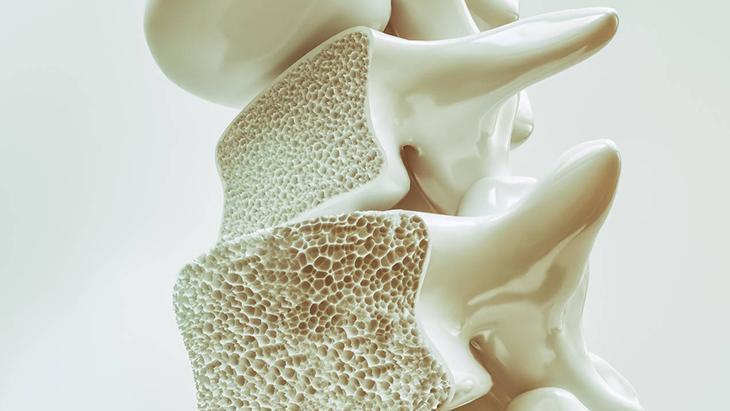

Osteoporoz ya da bilinen ismiyle kemik erimesi, vücudumuzdaki kemiklerin sertliklerinin azalıp kalitelerinin bozulması sonucu daha zayıf hale gelmesi ile ortaya çıkan sistemik bir hastalıktır. Kısaca kemiklerin kütlece azalmasıdır. Osteoporoz menopozdan sonra, bazı hastalıklar veya ilaç kullanımından sonra ortaya çıkan yaygın metabolik bir kemik hastalığıdır.

İlk dönem osteoporozda hasta, herhangi bir belirtiyle karşılaşmasa da bu durum zamanla değişir. Hastalık ilerledikçe kemik dokusunun direnci geri dönülmez şekilde azalır ve kemiklerde ciddi ağrılar görülebilir. Hastanın sırtında kamburluk oluşur ve kişinin boyu kısalmaya başlar. Kamburluk arttıkça göğüs ve karın boşluğunda daralmalar artar. Zamanla aktivite sırasında nefes almada zorlanmalar ortaya çıkar. Çok daha ileri safhalarda ise kemiklerde görülen kırılmalar en sık görülen komplikasyonlardan biridir.

Düşük kemik yoğunluğu ve kemik yapısında bozulmayla karakterize ve kemiğin kırılmaya eğilimini artıran sistemik bir hastalık olan osteoporoz, daha çok kadınlarda görülmektedir. Bunun nedenini ise şöyle açıklamak mümkün. Öncelikle erkeklerin kadınlara oranla daha kısa ömürlü olması ve erkeklerde kemik kütle oranının yüksek olması önemli bir etkendir. Aynı zamanda erkeklik hormonu olan testesteronun kemikler üzerindeki koruyucu etkisi ve kemik erimesini hızlandıran menopoz döneminin erkeklerde olmaması da bu hastalığın kadınlarda daha fazla görünmesinde etkin rol oynar.

Osteoporoz tanısı, kemik mineral yoğunluğun ölçümü ile konulur. Kısa süren ve ağrısız bir işlem olan mineral yoğunluğu ölçümü üç farklı kategoriye ayrılır. Bunlar; normal kemik kütlesi, düşük kemik kütlesi -2,5’a kadar olanlar (osteopeni) ve -2,5’dan küçükse osteoporozdur. Ölçüm sonunda kişinin kemik mineral yoğunluğu ne kadar düşük çıkarsa kemik erimesine yakalanma riski de o kadar yüksek demektir.Eğer ölçümler sonucunda sadece osteoporoz olduğunuz ortaya çıkarsa dışarıdan alacağınız D vitamini ve kalsiyum ayrıca önerilen egzersizleri yapmanız yeterlidir. İleri safhalar için ise hastalığın şiddetine göre daha farklı tedavi yöntemleri uygulanır.